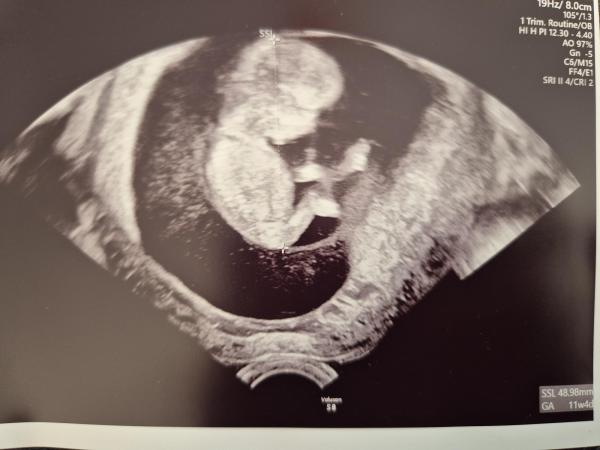

Ich sitze hier mit Freudentränen, es sieht diesmal tatsächlich nach einem Happy End für uns aus, damit hab ich nach den letzten 3 harten Jahren nicht mehr wirklich gerechnet. Der erste Satz der Gyn war: Da ist aber jemand kräftig gewachsen ❤️ Die Bilder waren so unglaublich schön, ich konnte sogar das Gesicht erkennen. Bin etwas enttäuscht, dass mir diesmal nur ein Bild ausgedruckt wurde, da waren  so viele tolle Aufnahmen von allen möglichen Körperteilen dabei. Bei meinem Sohn wurden mir damals 5 oder 6 mitgegeben. Und wir haben laut Ärztin ein sehr sportliches Baby, es war fleißig am turnen und sie meinte, dass es ihm wohl richtig gut gehe❤️ Ich hatte sofort unfassbare Muttergefühle und konnte nur denken: Du bist mein Baby und ich werde dich immer beschützen. Keine Ahnung, warum mir ausgerechnet das so durch den Kopf gespukt ist. Ich habe ehrlich gesagt ganz schön Bammel vor dem NIPT am Montag, dass uns doch noch etwas in die Quere kommt. Besonders erleichtert war ich auch, dass die Größe ganz genau gepasst hat bzw einmal auch einen Tag weiter berechnet wurde. Durch das Temperaturmessen weiß ich ja, wann der ES war, deswegen wäre rine Rückdatierung ein schlechtes Zeichen gewesen. Heute Nachmittag bin ich dann bei meiner tollen Hebamme, da freue ich mich auch schon drauf. Und morgen steht dann der nächste Termin beim Diabetologen an, der ist gespannt auf die Maße des Krümels, da ich ja jetzt seit 2 Wochen Insulin spritze.

Bild zu 1. Screening - Forum für Oktober - Mamis